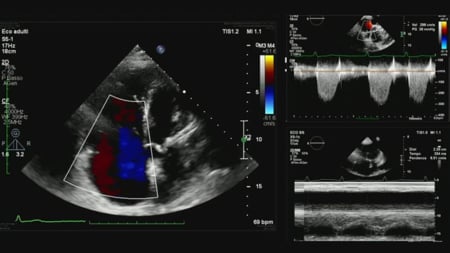

Procedural imaging for tricuspid valve interventions

15 Feb 2026 – From PCR Tokyo Valves 2026

Dedicated to procedural imaging for tricuspid valve interventions, this session elucidates anatomical and pathophysiological features critical for successful transcatheter procedures. It emphasizes technical aspects of TEE and ICE imaging, including 3D multiplanar reconstruction, and offers case-based learning to refine imaging skills and optimize procedural outcomes.